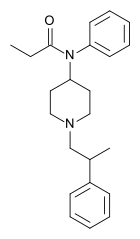

Anilidopiperidines